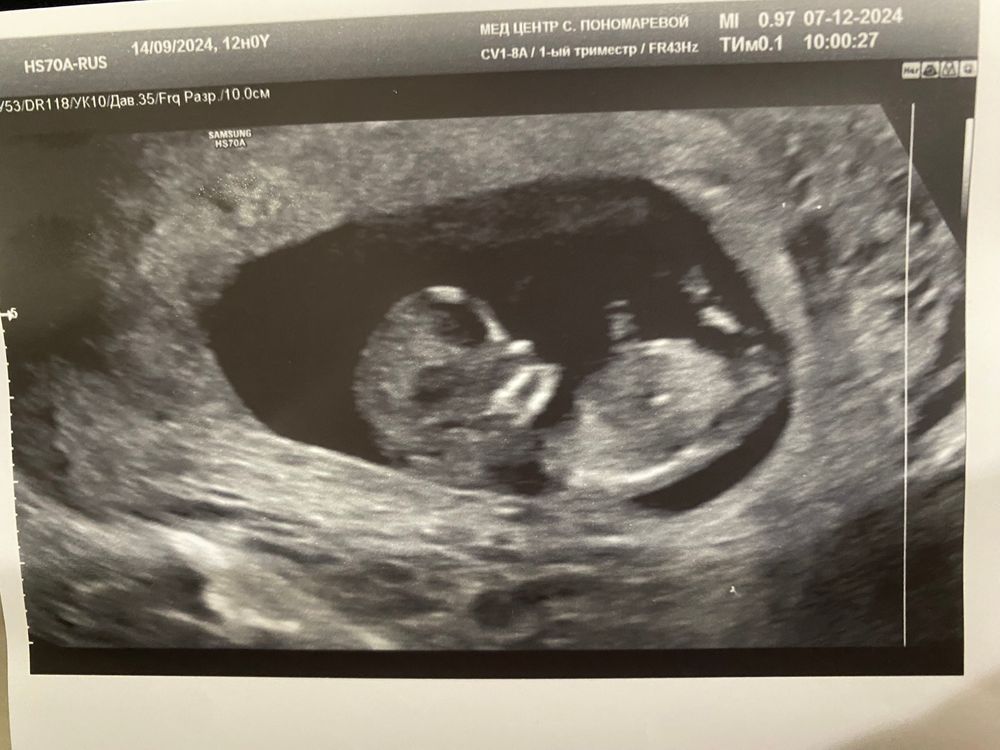

В 16 недель всех девчонок сказали верно, в 12 недель ошиблись. У вас я не вижу бугорка, нет его на фото

Тоже думаю ножкой закрылся. А так мне на первом скрининге сказали кто будет. Читала что если бугорок есть то это мальчик

Мне кажется, ножкой закрылся, полового бугорка не видно. Может, появится тут кто-то более глазастый)